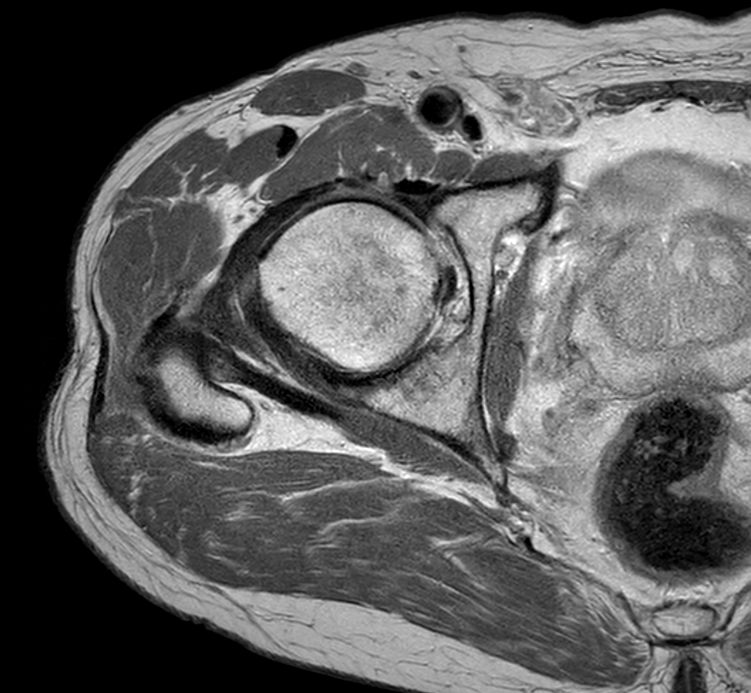

Axial PDw TSE

Axial PDw TSESmartSpeed

Axial PDw TSESmartSpeed High Resolution